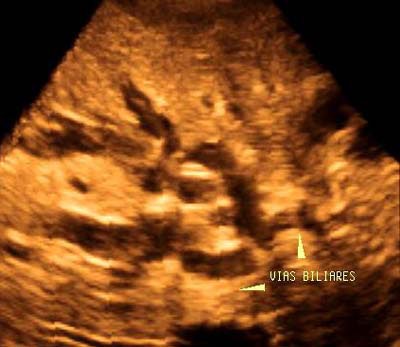

Acute cholangitis

A 35-year-old man with a history of alcoholism presented at the hospital with jaundice, fever, epigastric pain and dilatation, and irregularity of the intrahepatic ducts, as well as poor general condition. The 3D ultrasound study confirmed the existence of dilatation and irregularity of the intrahepatic ducts, which were filled with a thick substance, alteration in the liver parenchyma, and diffuse enlargement of the pancreas.

Planar imaging showed the existence of multiple very superficial liver abscesses, evidence of acute cholioangitis, and the development of chronic pancreatitis aggravated by the consumption of alcohol.

The sonographic diagnosis was confirmed by laboratory results and by endoscopic retrograde cholangiography.

![]() |

| Figure 6a. Volumetric reconstruction using a surface-rendering technique enabled clear visualization of the complete dilated intrahepatic hepatic biliary tree, which demonstrated irregular contours and contained thick material. |